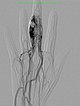

The nidus of the AVM in a magnified target image of the D III in digital subtraction angiography shows significant increase in size compared to the old angiographies (not shown). DSA images after transarterial antegrade puncture of the brachial artery with hypervascularized AVM of the middle and distal phalanx.